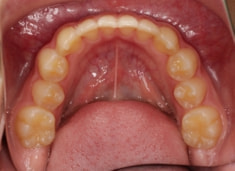

治療法:上顎急速拡大装置+クリアスナップ+フェイスマスク+上顎3番は開窓牽引CT写真にて位置確認